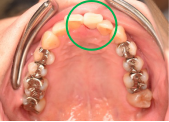

女性Mさん 40代(オールセラミック冠)

主訴

上の前歯が欠けた。

治療内容

神経をとる治療をし、根管治療後、ファイバーコアを入れ、オールセラミック冠を被せました。

所感

右前歯がむし歯で大きくかけていました。レントゲンを撮り詳しく診てみると、むし歯が深く、神経をとる治療が必要なことがわかりました。被せ物は、メタルフリーの治療を希望されましたので、ファイバーコアを入れオールセラミック冠を被せました。右上にむし歯があります。今後、そこの部分に取り組んでいきます。

オールセラミック冠1本:¥104,500(税込)

Before

むし歯が深く、神経に到達するむし歯でしたので、根管治療をしました。

After

根管治療終了後